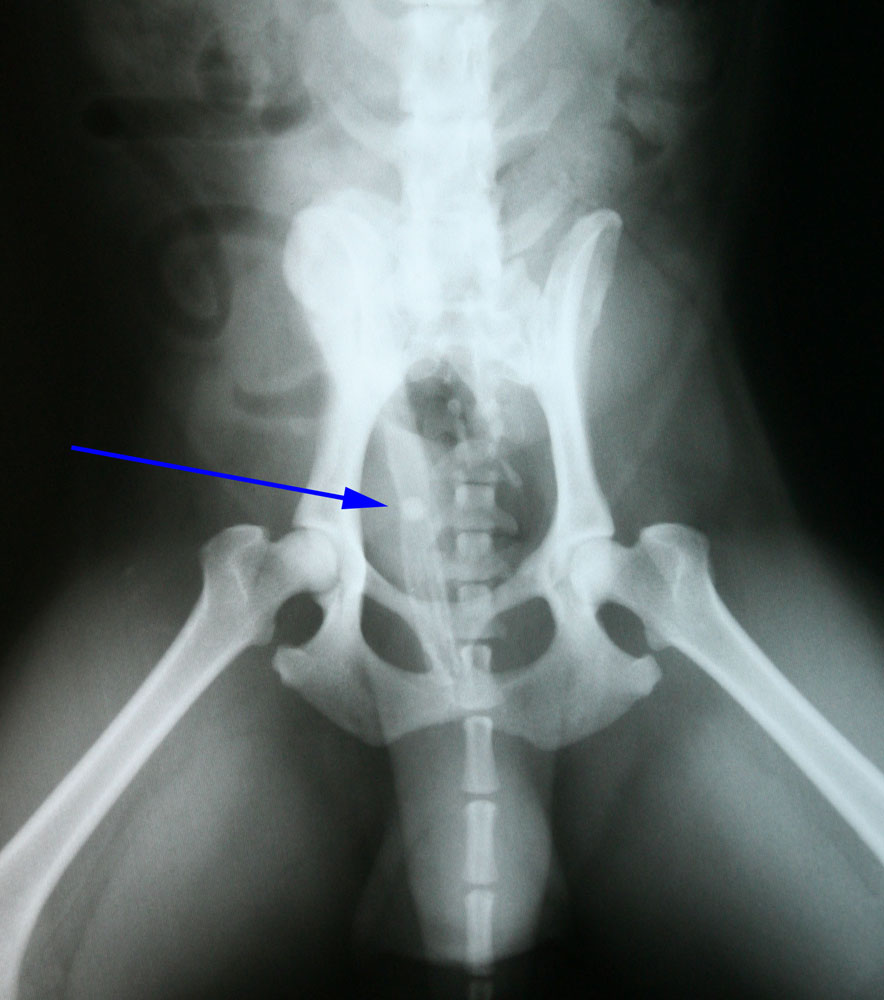

Hierna hebben we een urinekatheter ingebracht die na 4 cm vastliep op een harde structuur. Op de röntgenfoto is er bij de pijl een blaassteen te zien die vastgelopen is in het penisbotje.

Na verder onderzoek verricht te hebben kwamen we tot de conclusie dat er in de blaas zelf nog wat gruis zat en mogelijk zeer kleine steentjes.